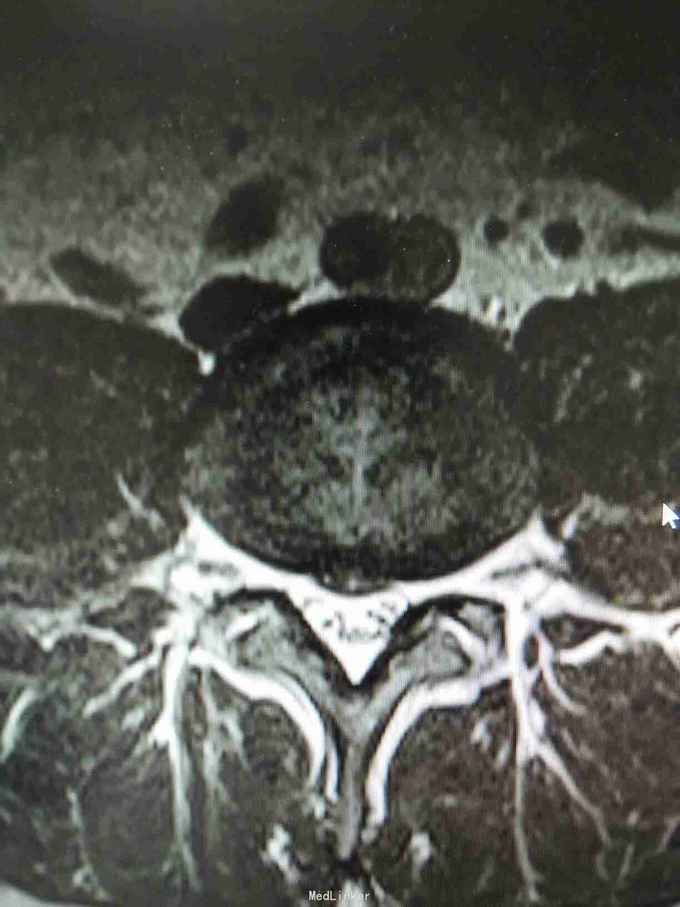

腰椎间盘突出 腰椎间盘突出症 骶管囊肿

1:腰椎间盘突出症2:骶管囊肿

该患者L4/5椎间盘中央突出,L5/S1椎间盘向左突出。手术右侧L4/5,L5/S1开窗,见骶1神经根与骶管囊肿粘连,压迫变性,水肿,变粗硬化。